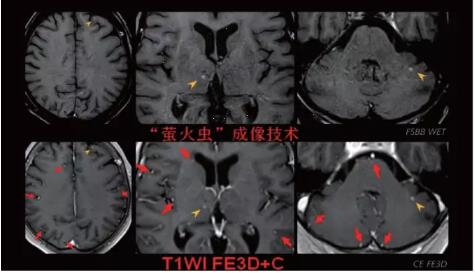

見所未見 微小腫瘤無處遁藏——

“螢火蟲”成像技術(shù) 顱內(nèi)腫瘤微小病灶檢出新發(fā)現(xiàn)

此技術(shù)主要用于神經(jīng)系統(tǒng)惡性腫瘤,以及其他腫瘤腦轉(zhuǎn)移瘤篩查。傳統(tǒng)情況下做腫瘤腦轉(zhuǎn)移篩查,很容易漏掉5mm以下小病灶,臨床發(fā)現(xiàn)后干預(yù)治療比較晚,要實(shí)現(xiàn)2mm高空間分辨率和超薄層全腦掃描在保證信噪比的情況下需要很長時(shí)間大概十多分鐘,而且薄層增強(qiáng)序列顱內(nèi)血管呈高亮信號(hào),會(huì)干擾顱內(nèi)小病灶的觀察,血管和小病灶區(qū)分困難。佳能”螢火蟲”成像技術(shù)既可以實(shí)現(xiàn)高空間分辨率和超薄層(最薄可實(shí)現(xiàn)0.2mm)全腦掃描,掃描時(shí)間短,2-3分鐘即可實(shí)現(xiàn)全腦3D掃描,同時(shí)避免了血管高亮信號(hào)的干擾,對(duì)顱內(nèi)原發(fā)或繼發(fā)的微小腫瘤檢查有重大意義。“螢火蟲”成像技術(shù)具有磁敏感效應(yīng),對(duì)于亞急性血敏感敏感,可以區(qū)分出血和強(qiáng)化的腫瘤。